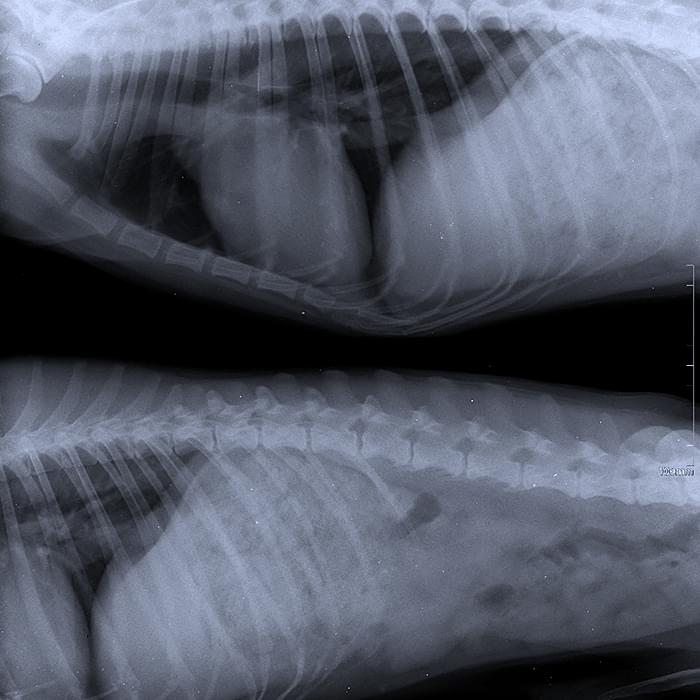

Icono de Radiografías Digital

Radiografía digital

Contamos con tecnología digital de punta para imágenes claras, que recibes directamente en tu correo electrónico o celular.